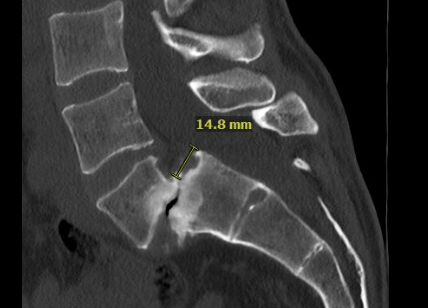

While my back had bothered me for quite some time, I found it worsening over the last five years, and, following a visit to my primary care physician and x-rays being taken, I was referred to a specialist for further imaging and consultation. The imaging revealed the grade 3 slippage of my vertebra at L5-S1, and I ended up meeting with six surgeons to determine the best course of action. Two of them recommended fusion from L4-S1 and the others including Dr. Huang recommended just the single level fusion. I picked Dr. Huang for the surgery because of his record of success and excellent reputation and that of the HSS.